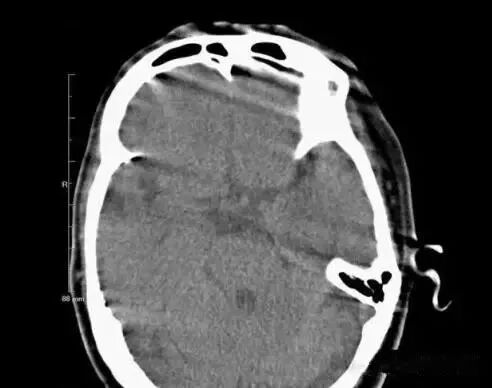

2.異物偽影:主要為密度差別極大的物體如金屬和人體組織一起掃描時所造成,偽影的特點是沿著高密度物體呈放射狀排列。有時圖像上不一定能直接看到目標(biāo)異物,但只要仔細觀察偽影的放射狀搏列方向,即能找到異物的來源。

2、金屬異物偽影:金屬異物產(chǎn)生的放射狀偽影,嚴重時明顯影響診斷。在掃描前應(yīng)去除病人體外隨帶的金屬物質(zhì),而病人體內(nèi)無法去除的金屬物質(zhì),如假牙或牙內(nèi)填充物、假肢、各類金屬支架等,可采用傾斜機架或掃描線的角度盡可能避開。目前也有研究采用某種算法抑制此類偽影。腹部常規(guī)掃描一般服溫開水,盡量不要服含碘造影劑。